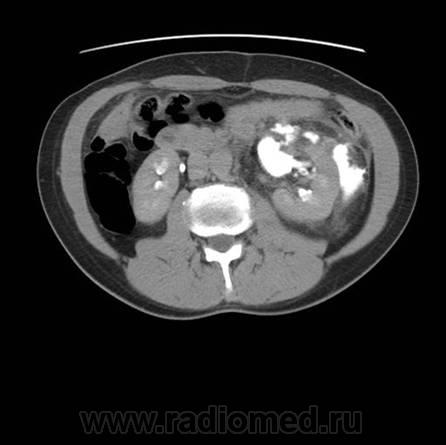

Травма. Боли в области поясницы.

Травматическое повреждение левой, по всей видимости, лоханки с разрывом и затеками контрастного препарата и мочи...